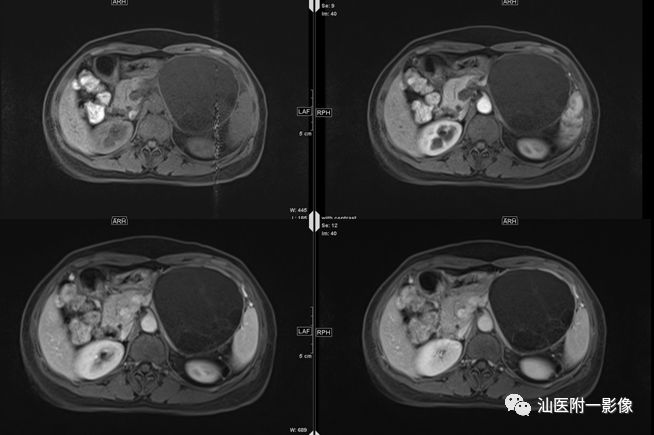

·男,15岁,上腹痛3天,加重半天

·3天前无明显诱因出现上腹痛,呈持续性痛。半天前症状突然加重。查体:全腹部腹肌紧张,左上腹部压痛及反跳痛明显。

·外院B超:左上腹囊性包块,考虑胰腺假性囊肿,未排其它

病例二 胰腺假性囊肿